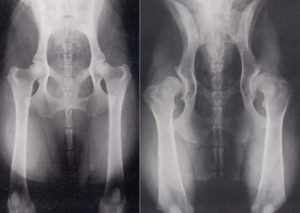

Неправильное формирование тазобедренного сустава

Виды ДТБС

Диагноз следует подтвердить данными сонографии или рентгена (у детей возрастом до 5 месяцев и старше, соответственно).

В качестве аппаратных методов применяется рентгенодиагностика (после 3-х мес.), ультрасонография (безопасно для любого возраста) – это диагностический стандарт обследования. Дополнительными служат – КТ, МРТ. Эти процедуры проводятся, когда решается вопрос о целесообразности хирургического лечения.

Основу диагностики составляет ультразвуковое обследование или рентген.

Ультразвуковая диагностика. Это скриннинговый анализ, который проводится всем деткам в возрасте от 0 до 3 месяцев. Более старшим младенцам, а также при оставшихся сомнениях, делается рентгеновский снимок.

Рентгенография. К сожалению, удержать неподвижно крошечного ребенка во время снимка довольно сложно. Кроме того, кости младенца отнюдь не такие плотные, как у взрослых, поэтому на снимках они просматриваются намного хуже.